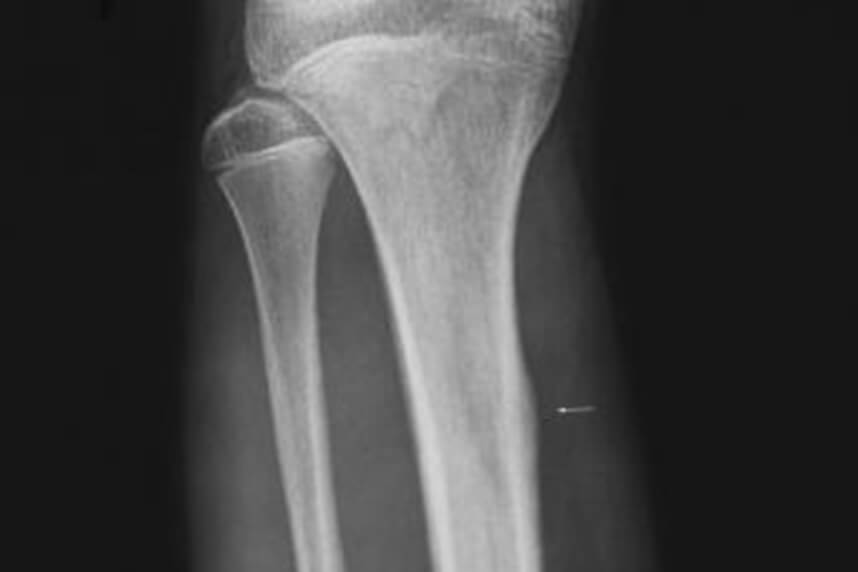

Fractura de tibie sau peroneu

Prin fractura intelegem o intrerupere a continuitatii osoase. Fracturile apar in momentul in care fortele care sunt aplicate pe un segment depasesc capacitatea acestuia de a opune rezistenta. Exista mai multe modalitati de a descrie o fractura:

- In functie de modalitatea de fracturare pot fi traumatice sau patologice (in special la varstnici din cauza osteoporozei sau in cazul bolii oaselor de sticla)

- In functie de modul de producere poate fi directa sau indirecta

- In functie de tiparul dupa care se rupe osul pot fi: transverse, oblice, spiralate sau longitudinale

- In funtie de fragmentele osoase rezultate pot fi compacte sau cominutive

- In functie de afectarea sau nu a pielii pot fi inchise sau deschise (osul iese in afara pielii)

- In functie de cat s-a rupt din os pot fi complete sau incomplete (fisuri)

- In functie de stabilitatea fracturii pot fi stabile sau instabile

Simptomele tipice ale unei fracturi sunt durerea, rigiditatea

articulara, impotenta functionala si hematomul. Diagnosticul este

de obicei confirmat prin raze X, iar tratamentul de urgenta este

dat la primul ajutor.